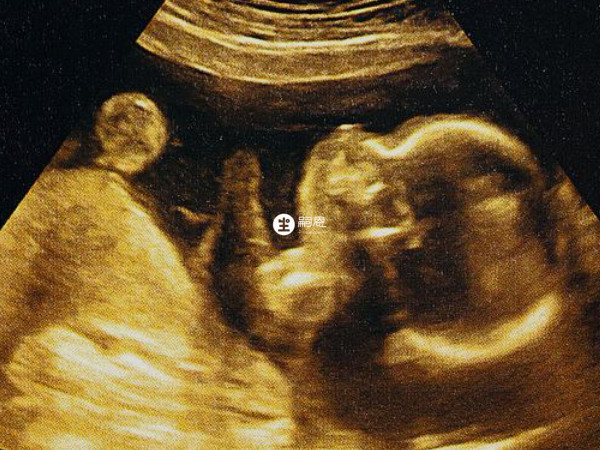

如果是正在備孕的人群,或者是孕期不超過3個月的孕婦,也可以考慮遵醫囑使用這種藥物,能夠補充葉酸,對預防胎兒神經管畸形有很好的效果。